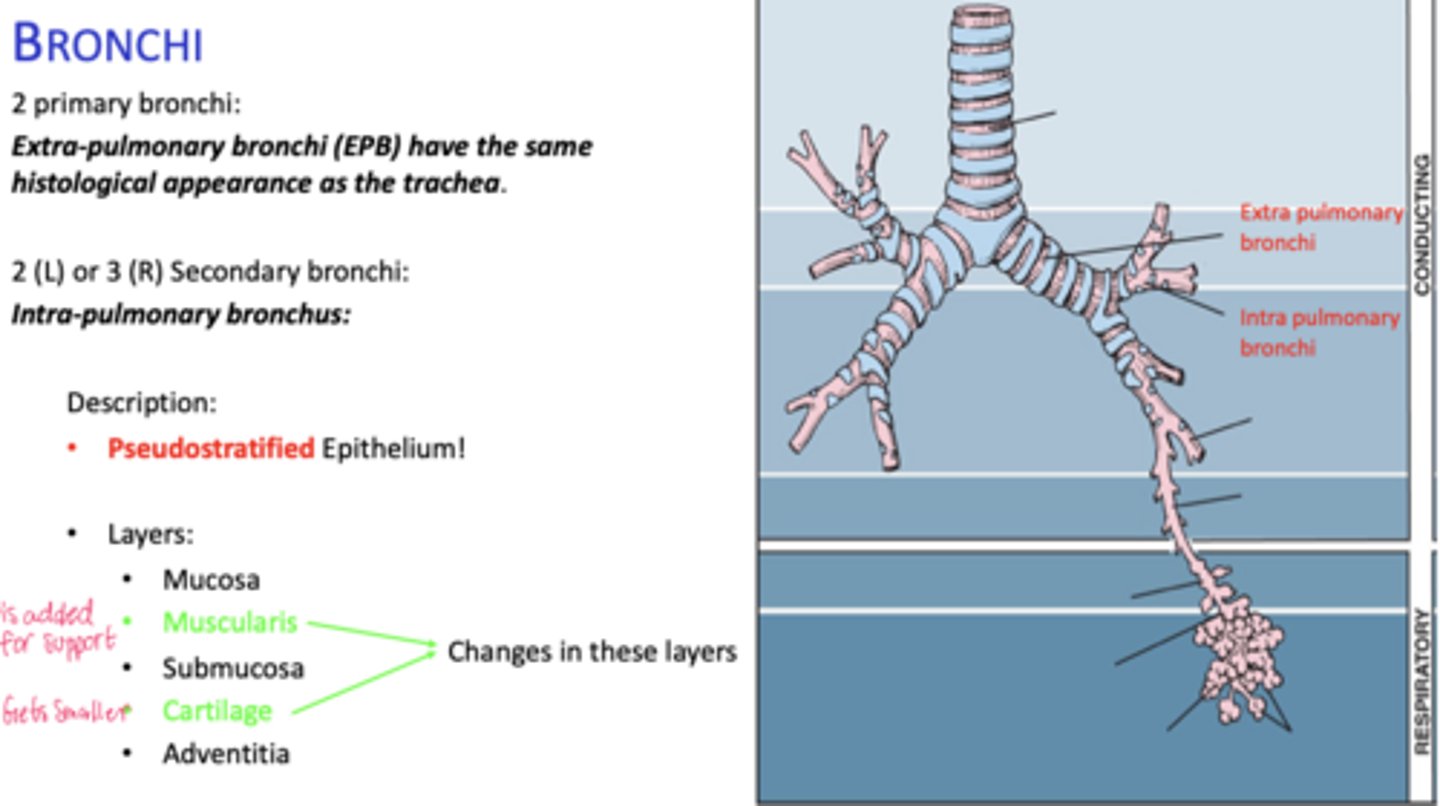

How many primary bronchi are present?

Two

How do extrapulmonary bronchi compare histologically to the trachea?

Same histological appearance.

How many secondary bronchi are in the lungs?

Two on the left, three on the right (intrapolumanry bronchus)

What happens to epithelial height as bronchial diameter decreases?

Cell height decreases.

What happens to cartilage in intrapulmonary bronchi?

Becomes discontinuous plates.

What muscle layer is present in intrapulmonary bronchi?

Spirally oriented smooth muscle.